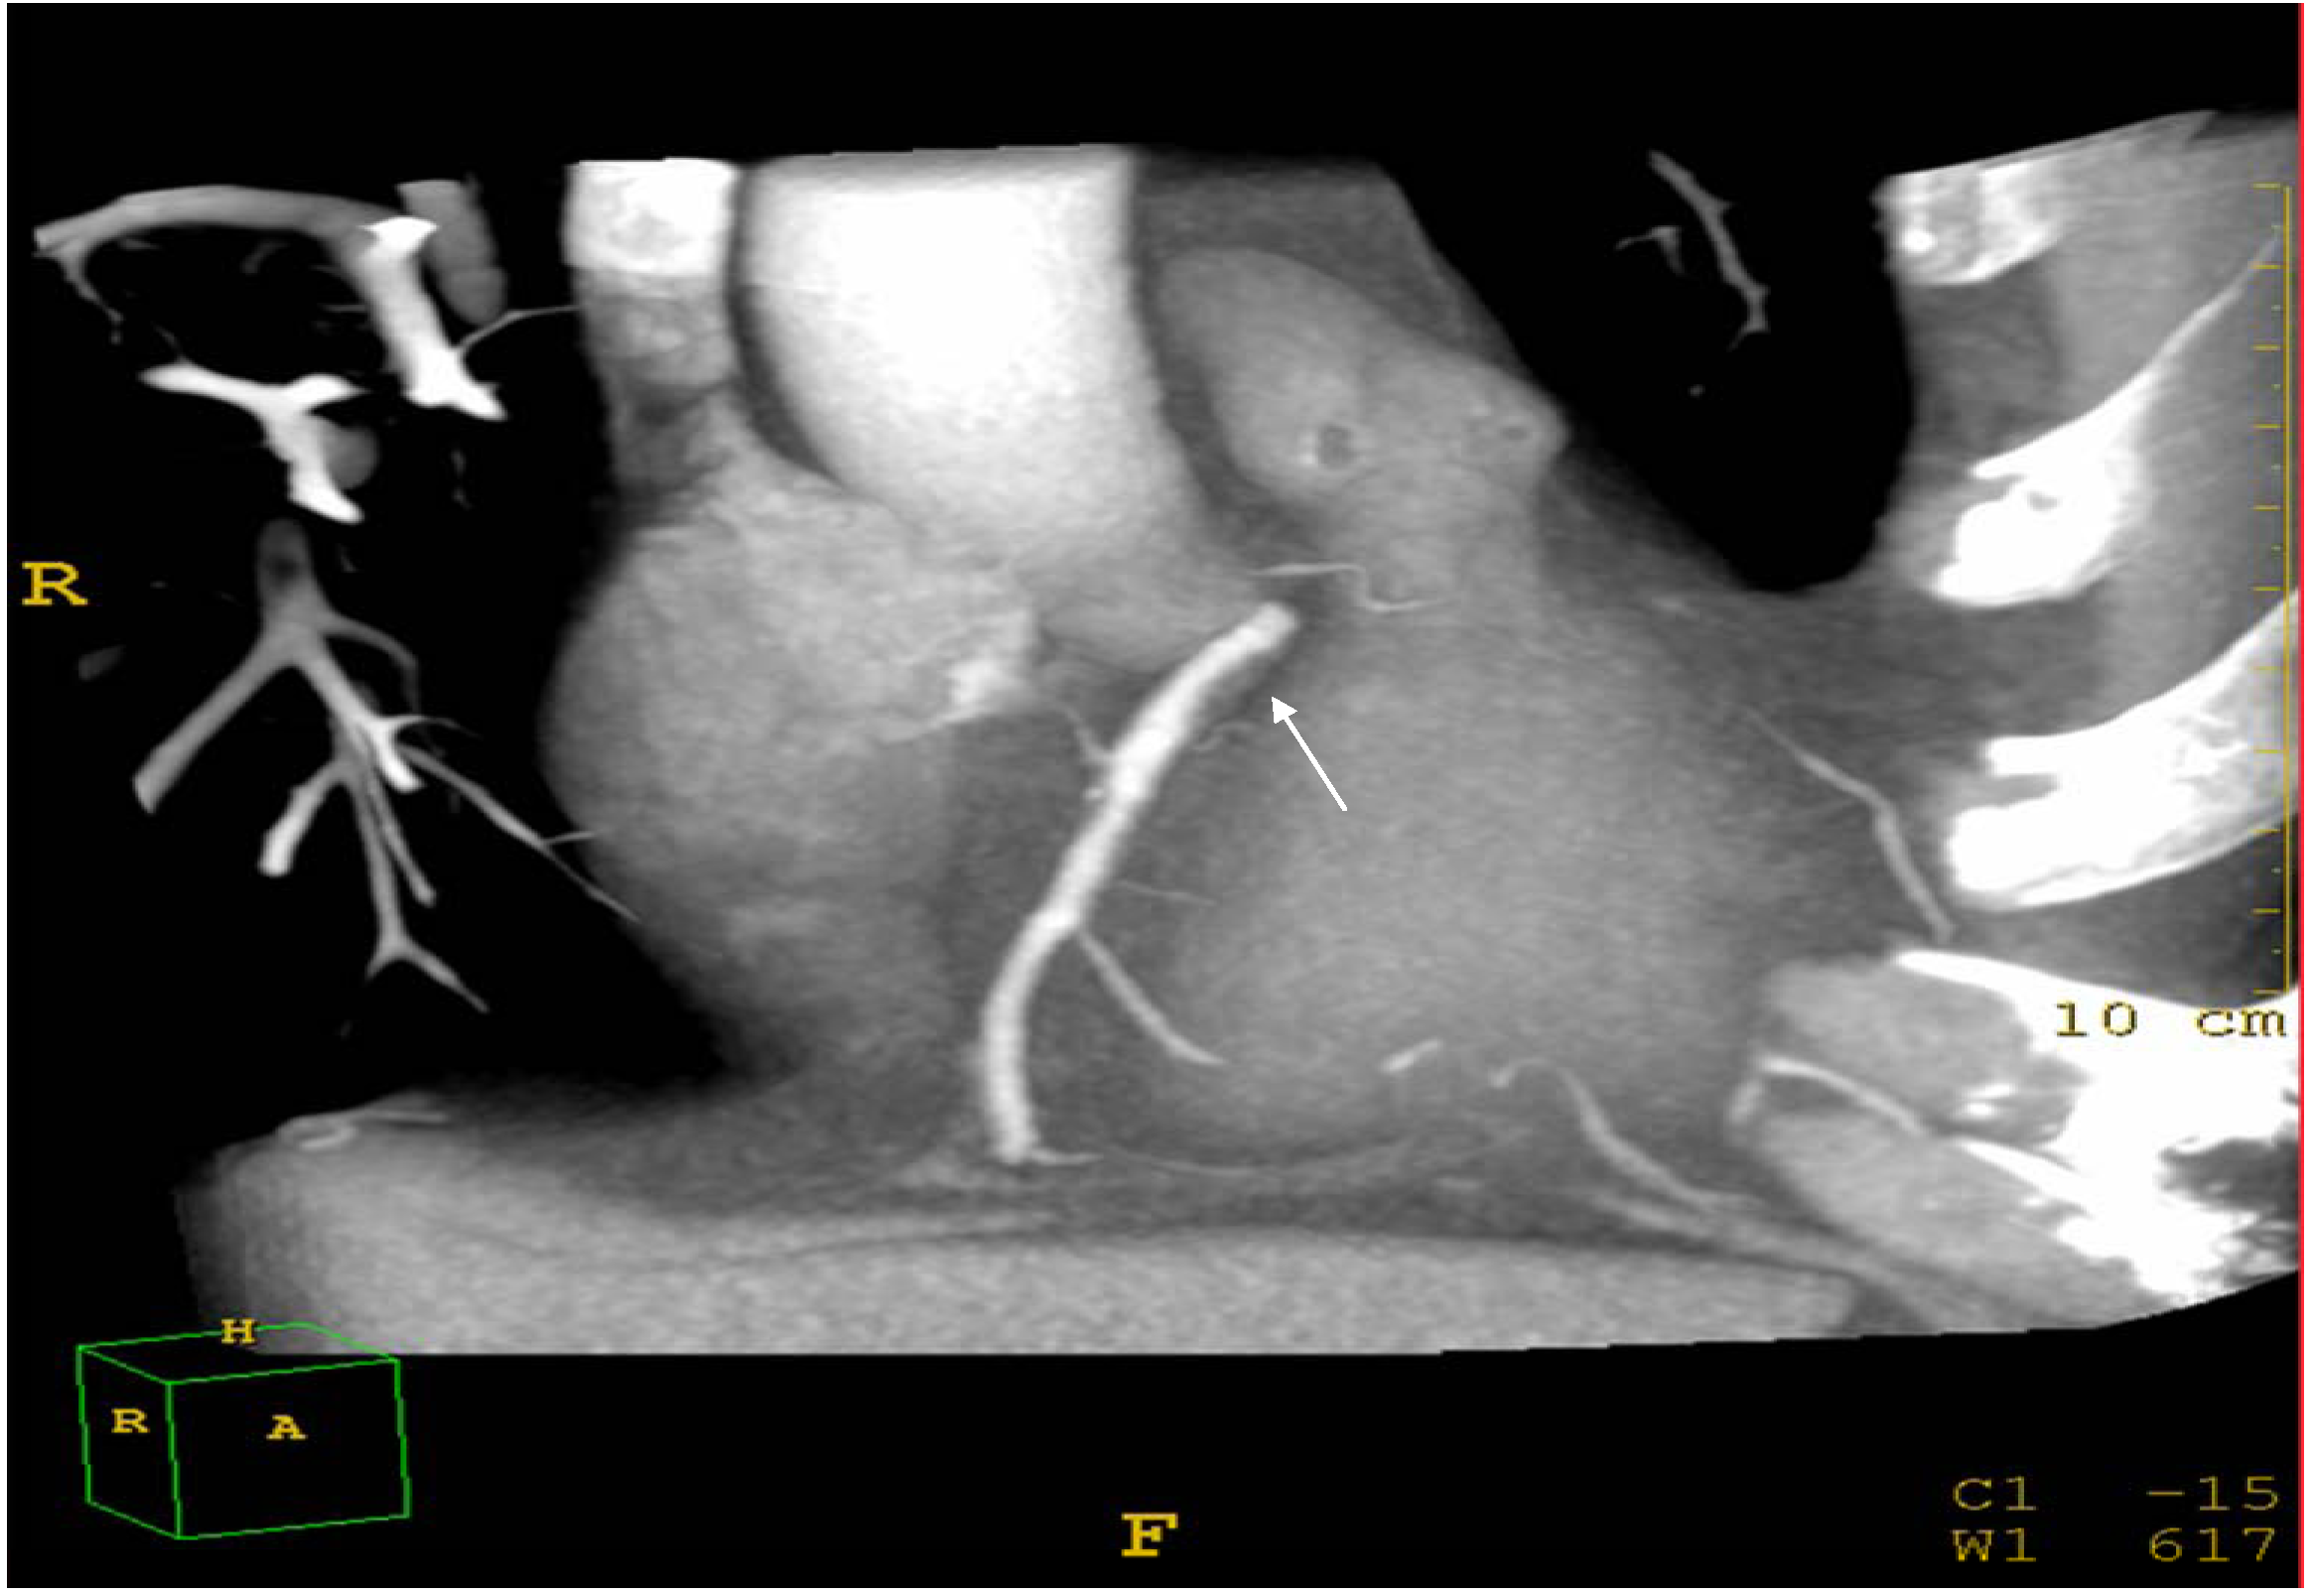

Assessment of coronary atherosclerosis was performed according to cardiac CT protocols. The patients were studied in the supine position. A bolus of 70–90 mL iomeprol contrast medium (400 mg/mL, Iomeron 400, Bracco, Milan, Italy) was injected intravenously (4 mL/s) followed by 50 mL bolus of saline via an 18 gauge catheter placed in the antecubital vein. Scan delay was determined employing an automatic bolus test in which the region of interest was located on the ascending aorta. Patients were instructed to maintain an inspiratory breath hold while CT data and electrocardiograph (ECG) trace were acquired. A 64-row scanner with a slice thickness of 0.625 mm (Brilliance Philips Medical Systems, Andover, MA, USA) was employed. For multidetector CT angiography, retrospective ECG gating was used, with heart rate adjusted gantry rotation of 350–500 ms to enable multi-segmented reconstruction. Temporal resolution was as low as 53 ms using 0.4 rotation and adaptive multicycle reconstruction. Pitch and tube currents of 200–500 mA were determined by patients’ weight. Beta blockers (propranolol 20 mg tab) were administered orally if resting heart rate was above 70 beats per minute. If heart rate was more than 80 beats per minute the patient was excluded from the study. Raw image data sets from all acquisitions were analysed by two independent specialists (AM > 20 years experience in cardiology and LA > 20 years experience in radiology) unaware of the hepatic and lipid profile of the patients. Intra-observer and inter-observer variability was measured by two readings of each observer. The two independent observers visually graded the degree of coronary stenosis (Figure 3).

Figure 3.

Cardiac CT: Example of soft (non calcified) coronary plaques at the proximal area of the right coronary artery (arrow).

The degree of stenosis was considered significant if >50% occlusion of the arterial lumen was present [29]. Plaques were classified as soft (none calcified) and calcified on a segmental basis according to plaque features, including volume, attenuation, and calcification pattern. In case of discrepancy between readers, a consensus reading was performed. Multi-segment reconstruction was performed with 0.6 slice thickness; 0.3 mm overlap; multiple phases of 70, 75, and 80%; and ECG editing (curved multiplanar reformat).